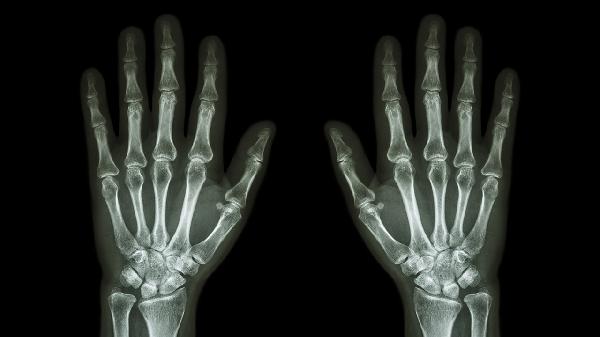

关节软骨退行性变引发的骨关节炎常见于中老年人,晨起关节僵硬、活动后疼痛减轻是典型特征。X线检查可见关节间隙狭窄、骨赘形成。治疗需减少关节负重活动,遵医嘱使用硫酸氨基葡萄糖胶囊、双醋瑞因胶囊等软骨保护剂,疼痛明显时可短期应用塞来昔布胶囊。